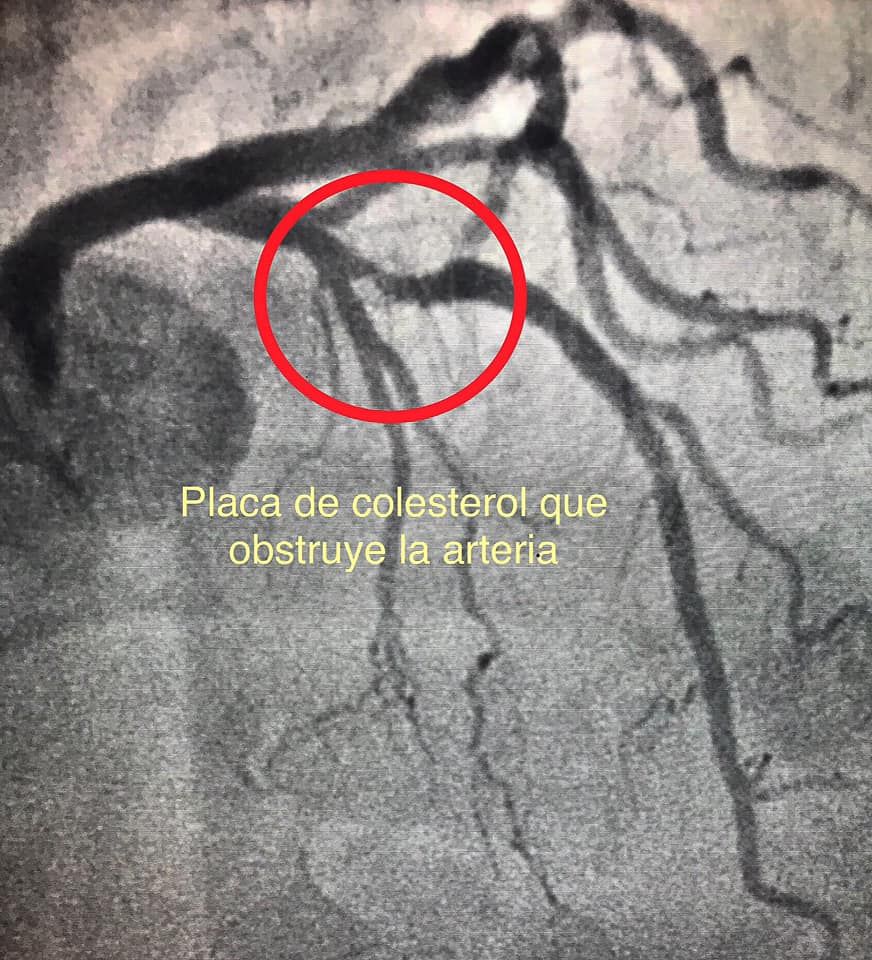

- Infarto agudo de miocardio

Cateterismo cardíaco terapéutico y diagnóstico